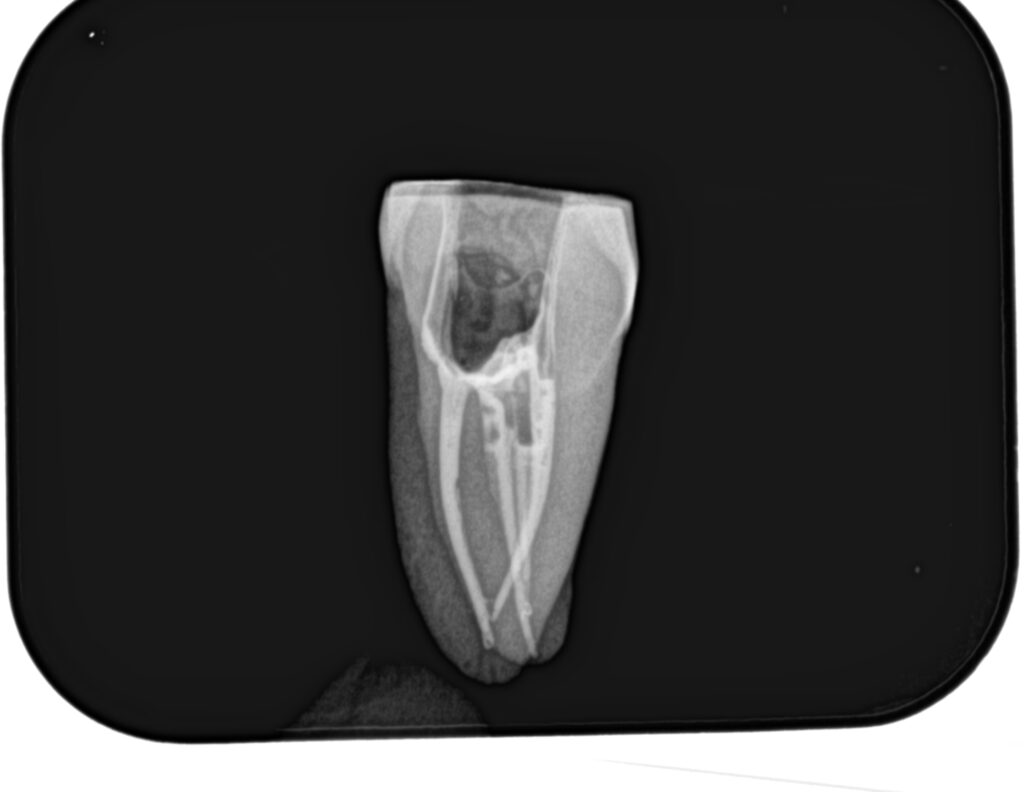

根管形成が終了すれば、根管充填だ。

その際に必要な物品は以下である。

日曜日は実習を行った。

土曜日の内容を投影した実習であった。

2本の歯牙で実習し、あっという間に1日は終了した。